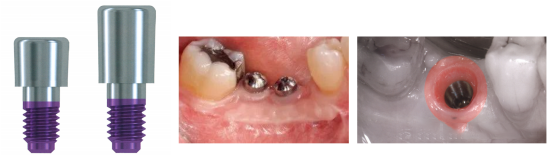

1、基台,也称之为愈合帽、愈合螺丝,在非潜入式种植,或潜入式种植二期手术暴露种植体后旋入种植体,形成种植体的穿黏膜过渡带,在戴入修复体之前引导种植体周围软组织愈合。愈合帽上方穿出黏膜进入口腔内,防止食物残渣和异物碎片等进入基台连接区,有利于软组织愈合和形成种植体颈部周围软组织封闭。因此愈合帽也被称为穿黏膜延伸或穿黏膜基台。根据种植体平台直径不同,愈合帽的直径也有差别。愈合帽有引导上皮组织生长、形成沟内上皮的作用,有的种植体系统也将其称为牙龈成形器。

①上宽下窄,软组织在愈合基台的不同高度成形,所形成的牙龈袖口直径也不同。

②最大直径应尽可能与天然牙颈部直径相接近;与天然牙之间应有1.5mm的距离,相邻两颗愈合基台之间应有3mm的安全距离;

①愈合基台的直径决定穿龈袖口的直径,同时也决定着修复基台穿龈的直径。愈合基台直径太小,则穿龈袖口较小,修复基台穿龈的直径相对减小,如果牙冠较大,则可能形成悬突,容易引起黑三角及承受咬合力时而发生折断;而如果穿龈较大,则可能致外冠瓷层变薄,致强度不够,而断裂;所以选择合适的愈合直径也至关重要。

②合适的愈合基台的直径应近似于天然牙颈部的直径,而在美学区或咬合力较小的区域,则可小于天然牙颈部直径。

③在美学区应尽量使用个性化愈合基台(个人观点),或使用直径小一些的成品愈合基台。前牙美学天然颈部的轮廓类似于三角形而成品愈合基台称圆形,因此直径过大有压迫唇侧软组织风险,而造成牙龈退缩的可能;